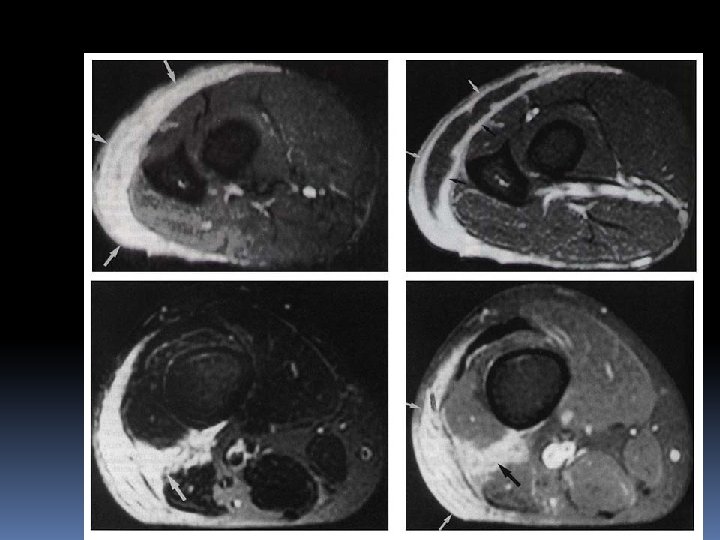

Necrotizing Fascitis Necrotizing fascitis is a fulminating inflammation of the fascia that results in thrombosis of the subcutaneous blood vessels and necrosis of the underlying tissue Necrotizing fascitis itself is generally divided into two broad Type I, caused by mixed aerobic/anaerobic bacteria, including enterococci and non-group A streptococci (usually C or G); and Type 2, caused by group A streptococci, either alone or in combination with other organisms

What are the Clinical Features of Necrotizing Fasciitis? The most common site of infection is the distal lower limb, although fascial extension up the leg is common. The progression is often alarmingly rapid from a silent or apparently minor process to a fulminant condition with clinical features of systemic toxicity, extensive destruction with threat to the affected limb, and even imminent death. The first clue may be unexplained and rapidly worsening pain By the time the bullae have appeared, there is usually already extensive necrosis.

How to diagnose Necrotizing Fascitis?

Ncrotizing Facitis is LIMB + LIFE threatening Immediate extensive surgical debridement must be done ASAP CLINDAMYCIN must be give , it also has antitoxin action